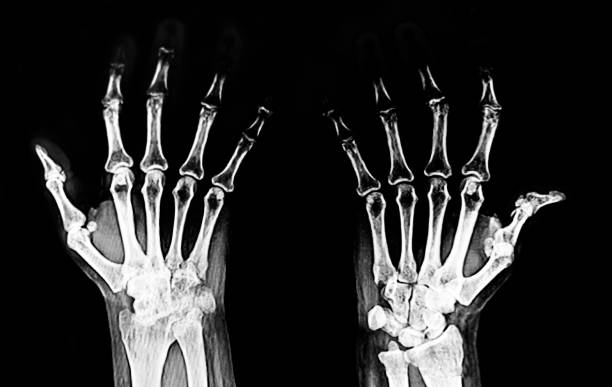

3. 류마티스 관절염 초기증상 - 관절 통증

류마티스 관절염 초기증상 세 번째는 관절 통증입니다 류마티스 관절염으로 인한 관절통은 운동과 휴식과 무관하지만 손가락과 손목 통증은 류마티스 관절염에서 흔하게 나타나나 통증은 발목, 무릎, 엉덩이, 어깨, 팔꿈치와 같은 관절과 손목, 팔꿈치와 같은 좌우 관절에서도 발생합니다.

10. 류마티스 관절염 초기증상 - 뻣뻣한 손과 발

류마티스 관절염 초기증상 열 번째는 뻣뻣한 손과 발입니다. 류마티스 관절염의 초기 단계에서는 후관절에서 증상이 나타난다. 해당 증상은 손가락과 손이 만나는 관절이나 발가락과 발 사이의 관절에서 시작되며 시간이 지남에 따라 이 뻣뻣함이 다른 관절로 옮겨갈 수 있습니다. 증상은 아침이 아닌 하루 중 언제든지 나타날 수 있습니다.